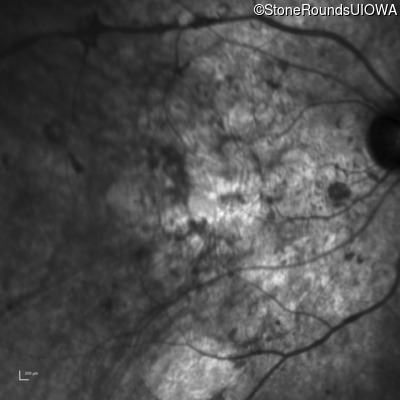

Age at visit: 33 years